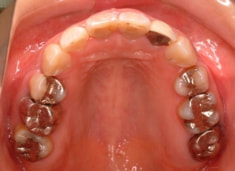

治療後(3年2ヶ月後)